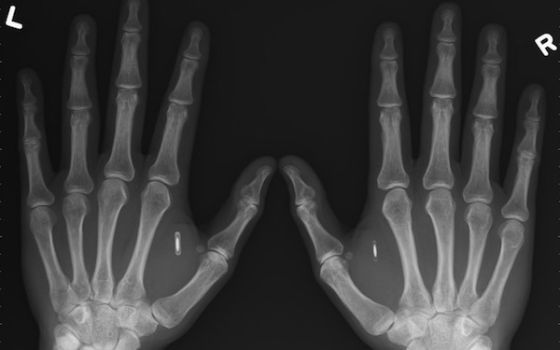

手部植入NFC芯片手部植入NFC芯片

稍微了解比特币的人知道,比特币的钱包秘钥关乎你钱财的安危,如果放在联网的电脑上,有被黑客窃走的危险,选择装在离线的U盘中,把它束之高阁,是最稳妥的做法。荷兰人Martijn Wismeijer由于创办了一家比特币交易公司,需要经常用到秘钥,索性将信息放在NFC芯片中,然后通过注射的方式打入手掌内,只要将手掌贴近感应器,即可完成秘钥输入。